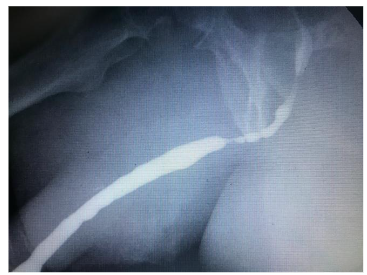

Urethral Catheter & CAUTI

The urethral catheter plays a leading role in the prevention of CAUTI. Its placement should be justified by an appropriate clinical indication: acute urinary retention, chronic urinary retention without bladder outlet obstruction, accurate measurement of urinary output in critically ill patients, perioperative use for selected surgical procedures, assistance in the healing of stage III and IV perineal and sacral wounds in incontinent patients, palliative care. The urethral catheter should be removed quickly once it is no longer needed.

In routine clinical practice, the professional should select the catheter and drainage system that fits the indication. Consider the material, design, caliber, length, and the ball’s capacity. Care should be taken with the techniques for insertion and removal of the catheter with adequate hand hygiene. All procedures must be recorded in writing.

The evidence-based European Association of Urology recommends: treating symptomatic CAUTI according to recommendations for complicated Urinary Tract Infections; perform a urine culture before starting antibiotic treatment in catheterized patients who have had their catheter removed; not medicating asymptomatic catheter-associated bacteriuria; treat catheter-associated asymptomatic bacteriuria prior to traumatic urinary tract interventions (e.g., transurethral resection of the prostate); replace or remove the catheter before starting antibiotic treatment; do not apply topical antiseptics or antibiotics to the catheter, the urethra or meatus; not using prophylactic antibiotics to prevent CAUTI; not routinely using antibiotic prophylaxis to prevent clinical urinary tract infections after catheter removal. The use of silicone catheters is associated with a lower risk of incrustation in indwelling catheterization.

The urethral stent is a self-expanding steel mesh that opens the urethral lumen. It is a procedure under vision, outpatient, with little or no bleeding and does not require a urethral catheter, the patient urinates immediately after stent implantation. It can be considered as an alternative to the indwelling urethral catheter in selected patients with bladder outlet obstruction. It’s a very good option in elderly patients with benign prostatic hyperplasia, chronic retentionists and with high surgical risk with multiple pathologies and polypharmacy or who refuse surgery.